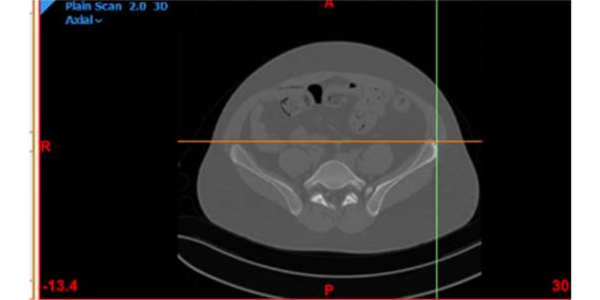

A newly married male 25 years old suffering from cancer of right pelvic bone. The difficulty in the case was the site of his cancer which was very rare, around the hip joint, which is major joint in body surrounded by vital organs.

Dr. Himanshu Rohela leading Onco Orthopedic surgeon in Mumbai, Maharashtra after studying the scan and his previous treatment records, concluded that the patient is suffering from cancer of right pelvic bone having tumor. The challenge was to save the leg thus using Patient Specific Cutting Guides and Patient Specific Hip implant. Incredible team discussed with Dr. Rohela, the designing and entire manufacturing process. It initially started with surgical planning and case simulation with the help of US FDA & CE approved Materialise Mimics software by superimposing CT & MRI DICOM data & Anatomical Model. As Anatomical model maintained 1:1 ratio with the anatomy, hence showed excellent detailing of the defect, the model was also used to design jigs & implant on actual bone, which further helped the pre surgical planning. Once the planning was finalized, the surgery was accompanied with not only Customized Implant but also Cutting guides & Jigs. Read more